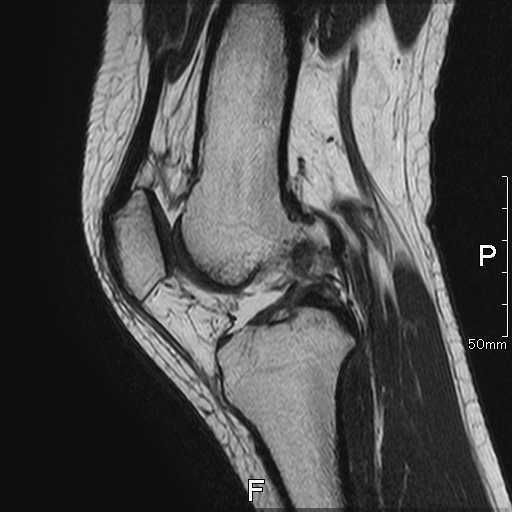

術後画像

| レントゲン | MRI |

| 異常なし | 再建靭帯の成熟をみとめる |